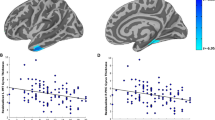

In maltreated youth, PTSD symptoms significantly and negatively correlated with right (Spearman’s rho=−0.37, p<0.008), left (Spearman’s rho=−0.32, p<0.03), total hippocampal (Spearman’s rho=−0.36, p<0.02), and left amygdala volumes (Spearman’s rho=−0.32, p<0.03). No other significant relationships were seen between PTSD variables, internalizing or externalizing symptoms, and trauma load, and ROIs. Please see Supplementary Tables 1 and 2 for Spearman’s rho correlations of variables for the non-maltreated and maltreated groups, respectively. Intracranial volume was significantly correlated with all ROIs (all p-values<0.01) in the non-maltreated and maltreated groups, respectively. Controls showed significantly greater correlations than maltreated youth between ICV and (i) total and left amygdala volumes; (ii) age; (iii) gender; and (iv) SES. Controls showed significantly greater correlations than maltreated youth between SES and (i) left ACC; and (ii) total, left, and right vmPFC. See Supplementary Table 3.

Confirmatory Analyses with VBM

The masked VBM analysis only showed greater gray matter intensity in controls than PTSD (p<0.05; corrected) in the left medial orbitofrontal cortex (x=−10, y=52, z=−26; t=4.33; 114 voxels) (Figure 2). We also performed a correlation between mean gray matter intensity of the orbitofrontal cluster obtained from the VBM and the number of PTSD symptoms and maltreatment types. The correlations were non-significant. We performed an additional exploratory whole-brain VBM analyses to examine whether there were any other brain regions which significantly differed between groups. This analysis showed no significant group differences at the corrected threshold.

(a and b) The confirmatory masked VBM analysis showing greater gray matter intensity in controls than maltreated youth with PTSD (p<0.05; corrected) in the left medial orbitofrontal cortex (MNI: x=−10, y=52, z=−26; t=4.33; 114 voxels). The mask, obtained from the FreeSurfer, included voxels within the orbitofrontal cortex, amygdala, hippocampus, and the anterior cingulate cortex. The masked images were analyzed with nonparametric permutation-based inferential statistics that included voxelwise regressors for age and sex.